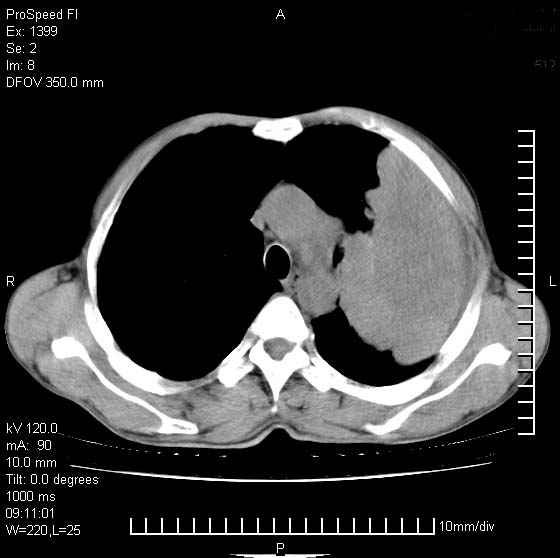

以下是引用rgsyyf在2007-1-19 11:05:00的发言:[br]左肺上叶见形态不规则巨大软组织肿块影,边缘呈分叶征,纵隔内隆突下见肿大淋巴结,右肺内另见一不规则结节影 .考虑:左肺周围性肺癌伴纵隔即右肺内转移.